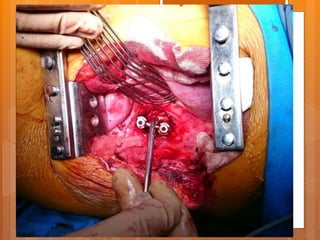

The segmental vessels

The parietal pleura

ALL L1 T12

T12-L1 disc

ALL

L1 T12